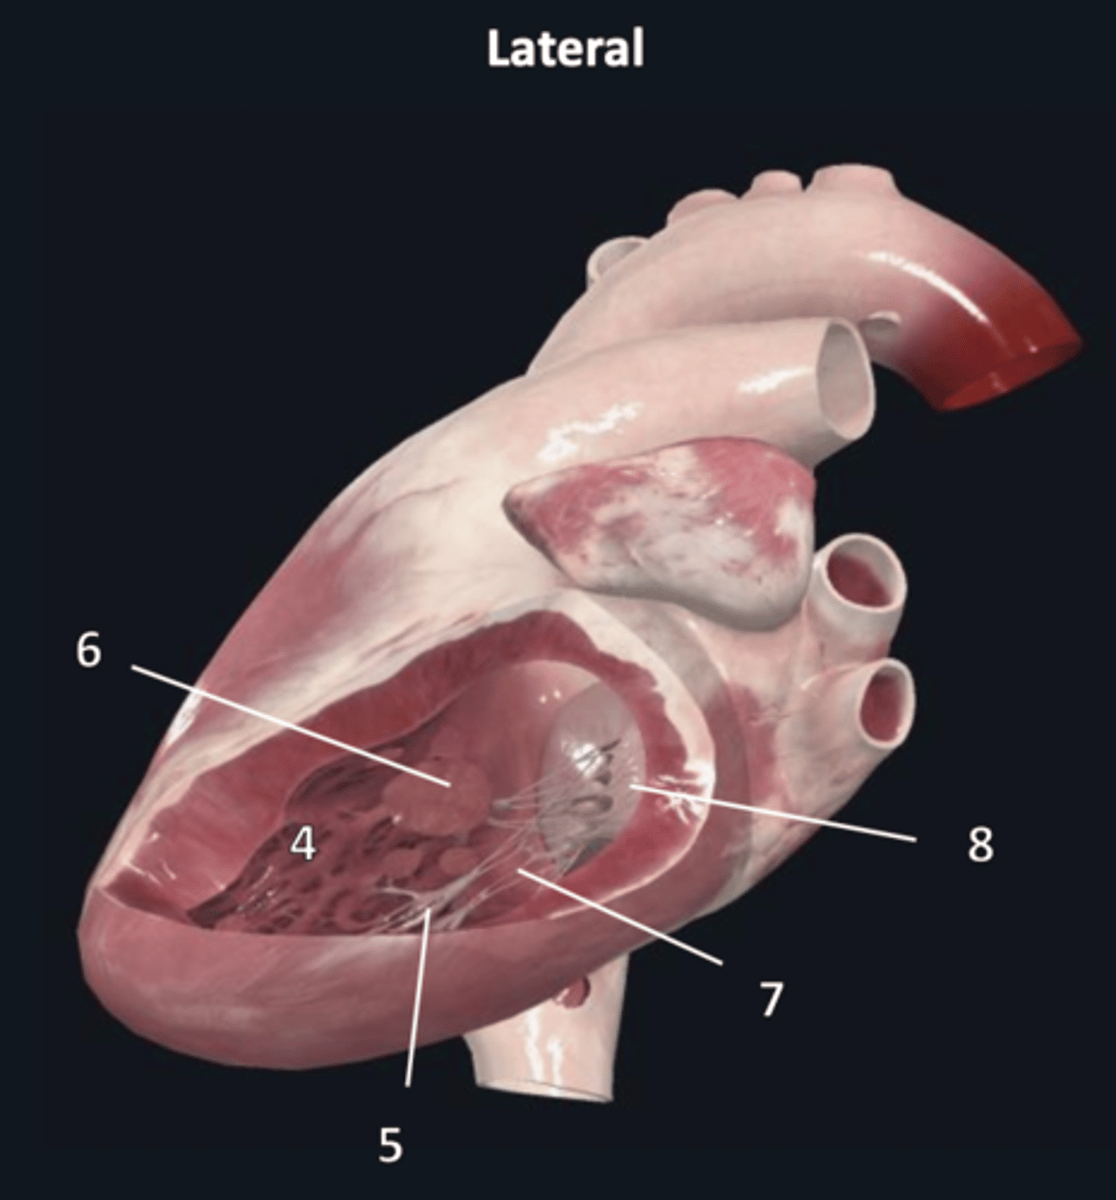

left atrium

1

left auricle

2

left ventricle

3

trabeculae carneae

4

inferior papillary muscle

5

superior papillary muscle

6

chordae tendineae

7

left atrioventricular valve

8 (opening)

aortic semilunar valve

9 (opening)